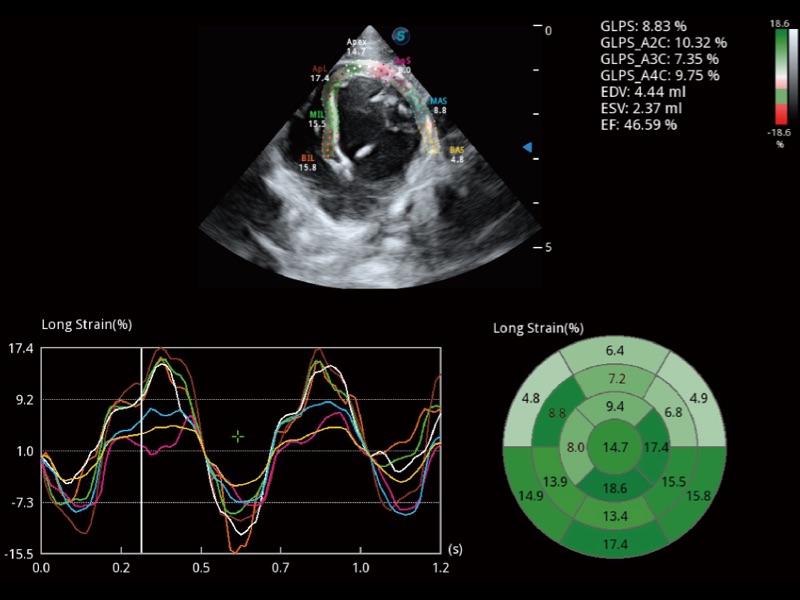

能够基于左心室壁追踪和辛普森法,自动计算射血分数,支持多个可移动点描迹,与手动测量相比,极大节省了动物医生的时间和精力。

实时用颜色表示心肌组织运动,观察和定量组织的运动情况,对快速检测与评估心肌的灌注和活性、电传导及心肌收缩和舒张功能等均能提供重要的诊断信息。